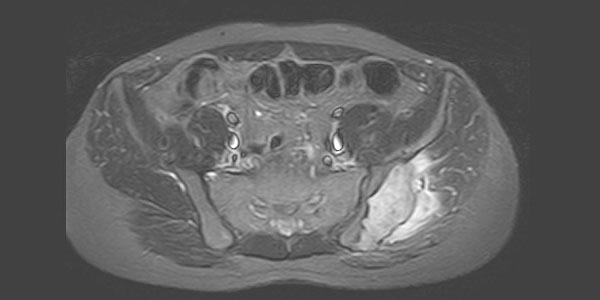

Chondrosarcoma is a malignant tumor of the bone that originates from cartilage tissue. Chondrosarcoma usually occurs after the age of 40 and is more common in men.